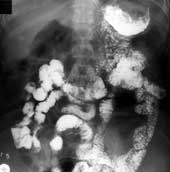

Резекция желудка с закрытием дуоденальной культи и соединение его оставшейся части с тонкой кишкой - вторая операция, выполняемая на дистальной части желудка (Бильрот-2). При этой операции культя желудка имеет разнообразную форму: чаще коническую, реже мешковидную, овоидную или цилиндрическую. Контуры желудка не только по большой кривизне, но и по малой вследствие наложения швов могут быть неровными. Это может симулировать дефект наполнения или формирование псевдодивертикула. Размеры культи желудка зависят от объема удаленной части органа и тонуса стенок. В раннем послеоперационном периоде она имеет несколько большие размеры, чем в отдаленный период. Рельеф слизистой оставшейся части желудка, в основном, сохраняет закономерности архитектоники свода и тела желудка, не выявляется каких-либо их особенностей вблизи соустья. Эвакуаторную способность культи желудка делят на три типа: непрерывный, непрерывный с переходом в порционный и порционный (Рис. 2, 3). Ускоренной считается полная эвакуация бариевой взвеси в течение первого часа; нормальной - отсутствие контрастного вещества через 1 - 1,5 часа после начала исследования и замедленной - опорожнение желудка за 2,5 часа и более. Обычно выявляется ускоренная эвакуаторная функция культи желудка и это, во многом, определяется удалением важного регулятора опорожнения - пилорической зоны. Наиболее физиологический порционноритмический тип опорожнения с сохранением нормальных сроков эвакуации остается только в случае экономной резекции органа. Каких-либо особенностей эвакуаторного процесса при разнообразных модификациях резекции желудка с формированием гастроеюностомии большинство авторов не отмечают.

Рис. 2. Непрерывный тип эвакуаторной способности желудка.

Рис. 3. Непрерывный с переходом в порционный тип эвакуаторной способности желудка.